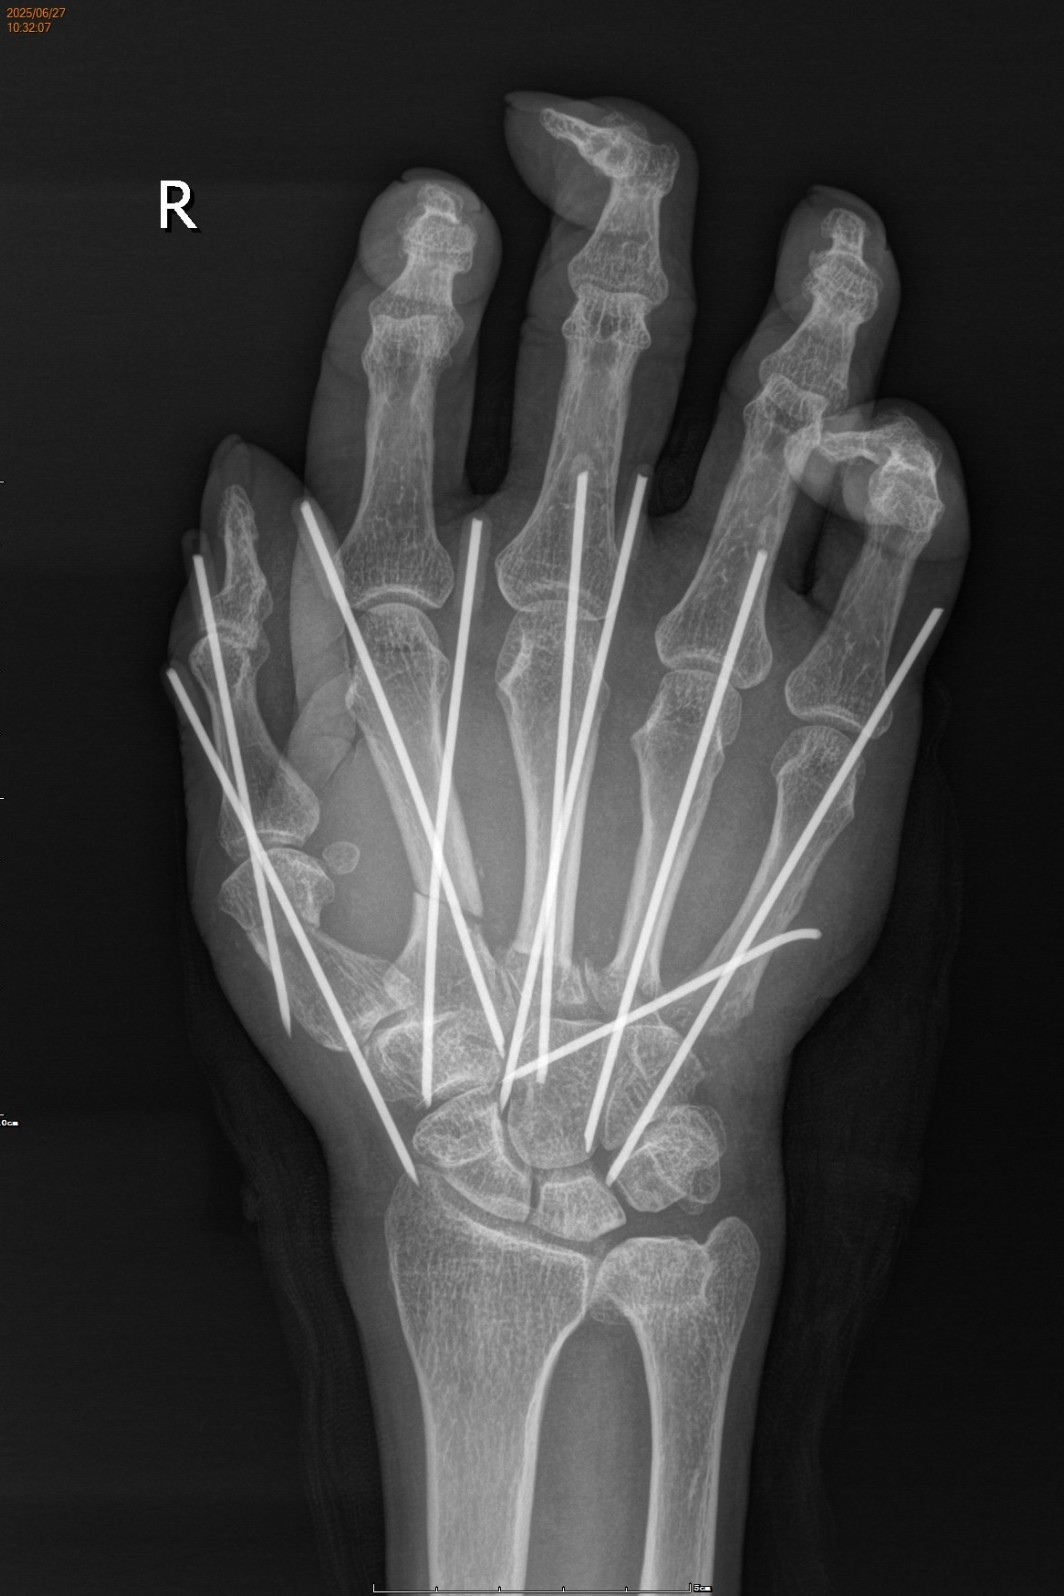

凭借丰富的临床经验和专业的医学知识,陈孝均带领团队很快确定了手术方案。在排除了相关手术禁忌后,一场与时间赛跑的“右手掌断肢再植术+游离前臂Flow-through静脉皮瓣修复手背创面+石膏外固定术”在臂丛麻醉下正式开始。

患者术前、术后影像学资料